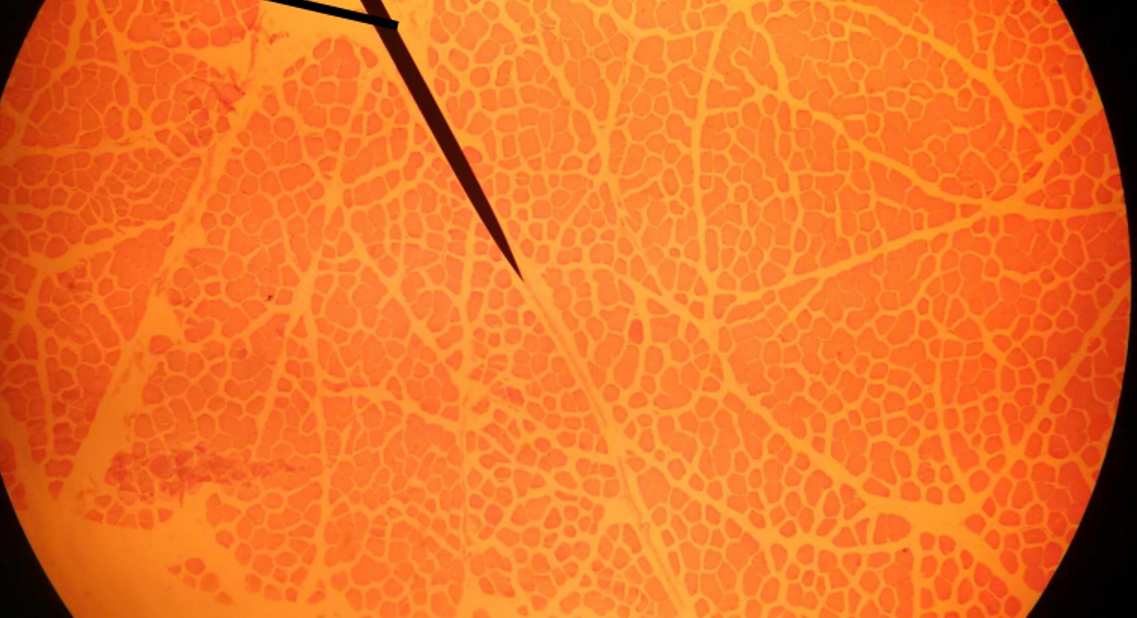

What muscle is this?

Skeletal muscle